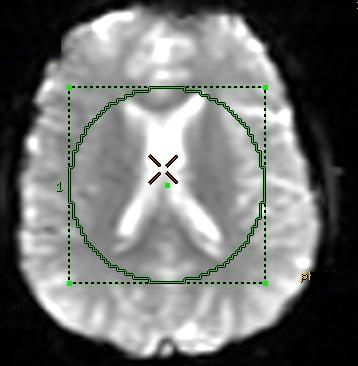

- From the MR Standard screen, click and drag the left threshold slider until the anatomy is outlined in green and all the anatomy inside the image displays green lines.

Figure 1. Sample of large ROI positioned over anatomy